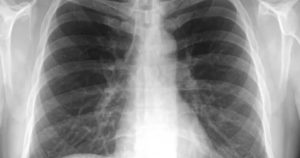

Здоровые лёгкие. Обзорный снимок грудной клетки

В норме лёгкие без изменений, корни хорошо визуализируются и не имеют патологических расширений. Диафрагмальный контур и синусы не имеют патологических признаков. Сосуды дают тень привычной конфигурации.

Суставы, кости и мягкие ткани в норме не изменены.

Приведённые выше данные расшифровки характерны для пациентов до пятидесятилетнего возраста. С возрастом происходят изменения, которые по-иному отображаются на рентгеновском снимке.